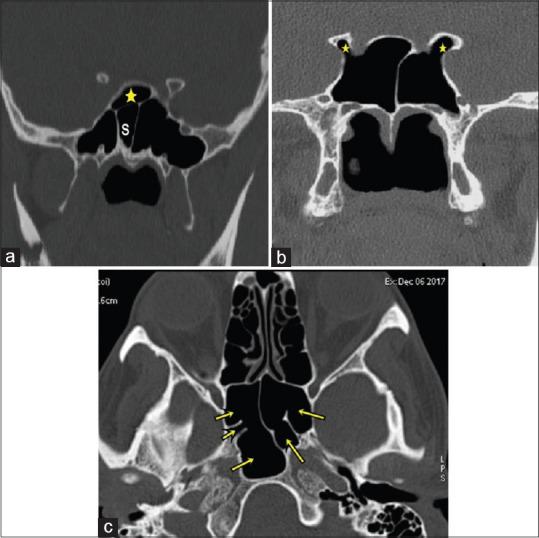

Among 250 study population, 100 were females and 150 males. Among these 423 cases of anatomical variants were observed. The most common anatomical variants were pneumatization of the middle nasal turbinates 30.73%. This is followed by agger nasi cells 21.64%, Haller's cells 22.91%, septal deviation 21.91%, and sphenoid sinus septation (20.18%).

CT is the gold standard in the radiologic investigation of the paranasal sinuses, sinonasal lesions, and inflammatory disease or pre- and post-surgical assessment. It has the capability of disclosing in greatest detail any anatomical variations, which could be causing or precipitating the sinusitis.